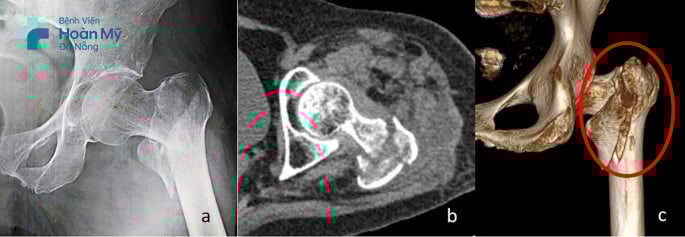

Người bệnh ngoại quốc H.A (60 tuổi) đến Bệnh viện Hoàn Mỹ Đà Nẵng do sưng đau nhiều khớp háng bên trái. Khai thác tiền sử, được biết cách thời điểm thăm khám 1 ngày, người bệnh bị ngã xe. Sau tai nạn, người bệnh bắt đầu đau và hạn chế vận động háng trái. Tại bệnh viện Hoàn Mỹ Đà Nẵng, người bệnh được chụp X-Quang, CT scan chẩn đoán và xác định bị gãy liên mấu chuyển xương đùi trái.

Hình ảnh gãy liên mấu chuyển xương đùi trái phức tạp trước phẫu thuật của người bệnh